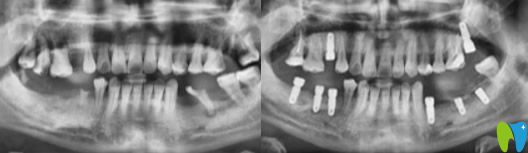

術(shù)前問題:下頜磨牙掉的只剩一顆,上頜情況也不容樂觀,并有多顆牙松動。

解決方案:通過數(shù)字化技術(shù),精準地在梁女士缺牙位置植入種植體,一些無法保留的牙齒采取了即拔即種治療,解決了她多年的缺牙問題。